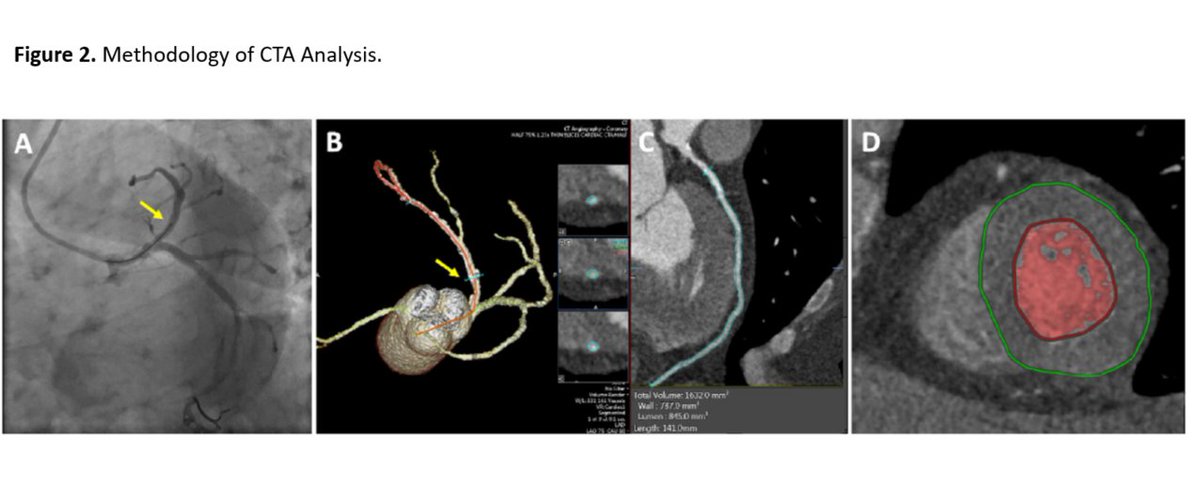

Zheng et al showed that the coronary geometry has clear phase-dependency, thus the phase dependency should not be ignored when CCT is used to quantify computational fluid dynamics-derived parameters. https://t.co/65ySbgQGR2

The results of this study by Chan et al emphasize the importance of patient-specific modeling in improving the accuracy of CT-FFR methodologies and validate the physiological rationale for deriving FFR non-invasively from CTA. https://t.co/68EEOaAjHX

In this second of the two-part review article, @PRodriguezMD et al assess the literature on CT-FFR and its integration with CCTA for evaluating heart disease. https://t.co/H3kH5CJH3v

This first part of a comprehensive review by @KashifAbbasSha1 et al discusses the methodologies for deriving fractional flow reserve (FFR) from CCTA, focusing on computational fluid dynamics (CFD) and AI techniques. https://t.co/FfpVFSJfYf